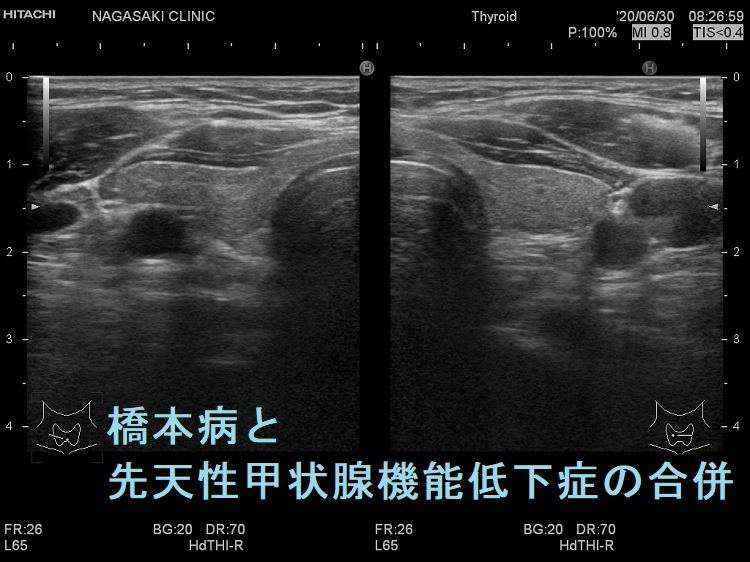

遺伝性甲状腺ホルモン合成障害に橋本病(慢性甲状腺炎)を合併

遺伝性甲状腺ホルモン合成障害に、橋本病(慢性甲状腺炎)を合併する事があります(橋本病も約70%は遺伝性です)。

あくまで仮説ですが、甲状腺ホルモン合成障害で血中サイログロブリンが上昇すると、それに対する抗サイログロブリン抗体産生が誘発され、橋本病が発症する可能性が考えられます。(第55回 日本甲状腺学会 P2-01-10 TSH 遅発上昇により新生児マススクリーニングをすり抜けた複合ヘテロ接合性DUOX2 異常症に橋本病を合併した女児例)

橋本病(慢性甲状腺炎)に遺伝性甲状腺ホルモン合成障害の軽症例を合併

橋本病(慢性甲状腺炎)を合併すると、遺伝性甲状腺ホルモン合成障害の軽症例がマスクされ、あたかも甲状腺機能正常橋本病による腺腫様甲状腺腫のように見えます(橋本病も約70%遺伝です)。